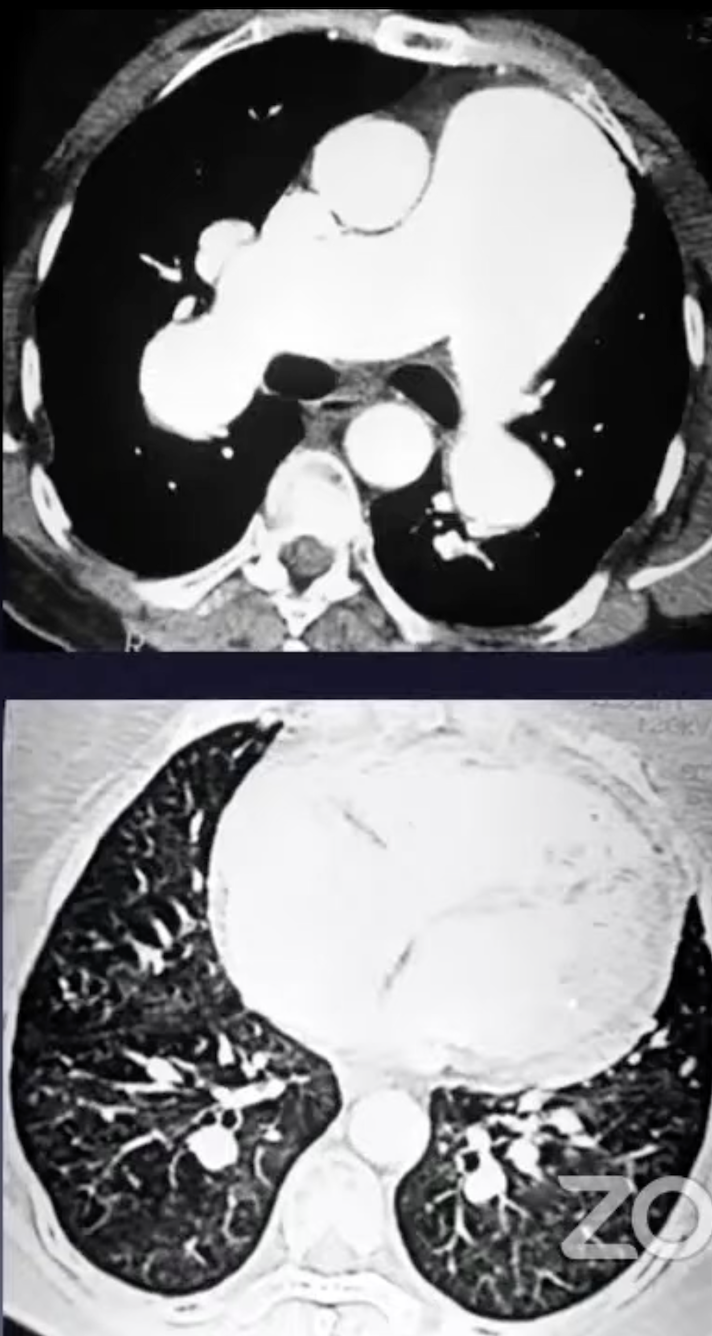

Hipertensão pulmonar

Relação artéria-brônquio

Hipertensão arterial pulmonar

- esquistossomose

Sinais de hipertensão arterial pulmonar